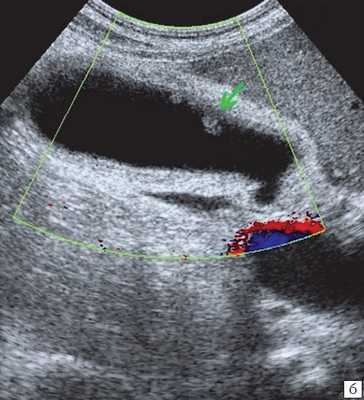

- УЗИ желчного пузыря. Эхогенная картина не слишком специфична и достаточно изменчива. На мониторе можно увидеть изменение структуры, толщины стенок, значительное увеличение объема пузыря. Внутри органа визуализируется скопление желчи, возможно с газовыми пузырьками, неоднородным осадком, хлопьями. В перипузырном пространстве обнаруживается выпот и скопление жидкости.